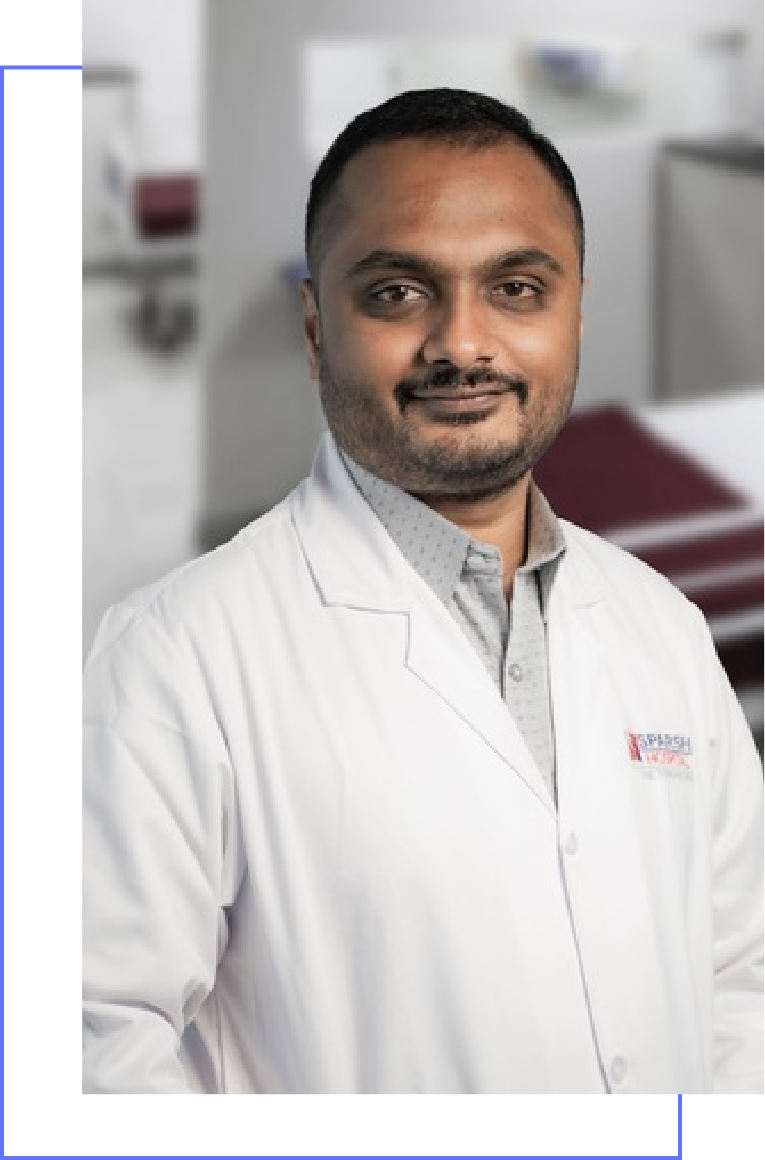

Dr. Vivek G

Consultant Pulmonologist

Dr. Vivek Gundappa is an accomplished Interventional Pulmonology and Respiratory Emergency Specialist, Pulmonologist specializing in Asthma and Chronic Obstructive Pulmonary Disease with 8 years of experience in the field

He earned his MBBS and MD (Pulmonary Medicine) from Rajarajeswari Medical College and Hospital. He further honed his expertise through a Fellowship in Interventional Pulmonology from AAS5 Friuli Occidentale – S. C. di Pneumologia, Pordenone, Italy.

Dr. Vivek Gundappa’s special expertise lies in interventional pulmonology, airway disease, pulmonary fibrosis and sleep medicine. Dr. Vivek’s approach to medicine is evidence based and he actively seeks to stay abreast of the latest advancements in his field. Dr. Vivek is especially skilled at Interventional Pulmonology and has trained in advanced airway and pleural procedures such as: Thoracoscopy, EBUS (Endobronchial ultrasound), Rigid bronchoscopy and advanced central airway procedures, Peripheral pulmonary nodule navigation and biopsy

MBBS and MD, From Rajarajeshwari Medical COllege

Fellowship in Interventional Pulmonology, From AAS5 Friuli Occidentale, Italy